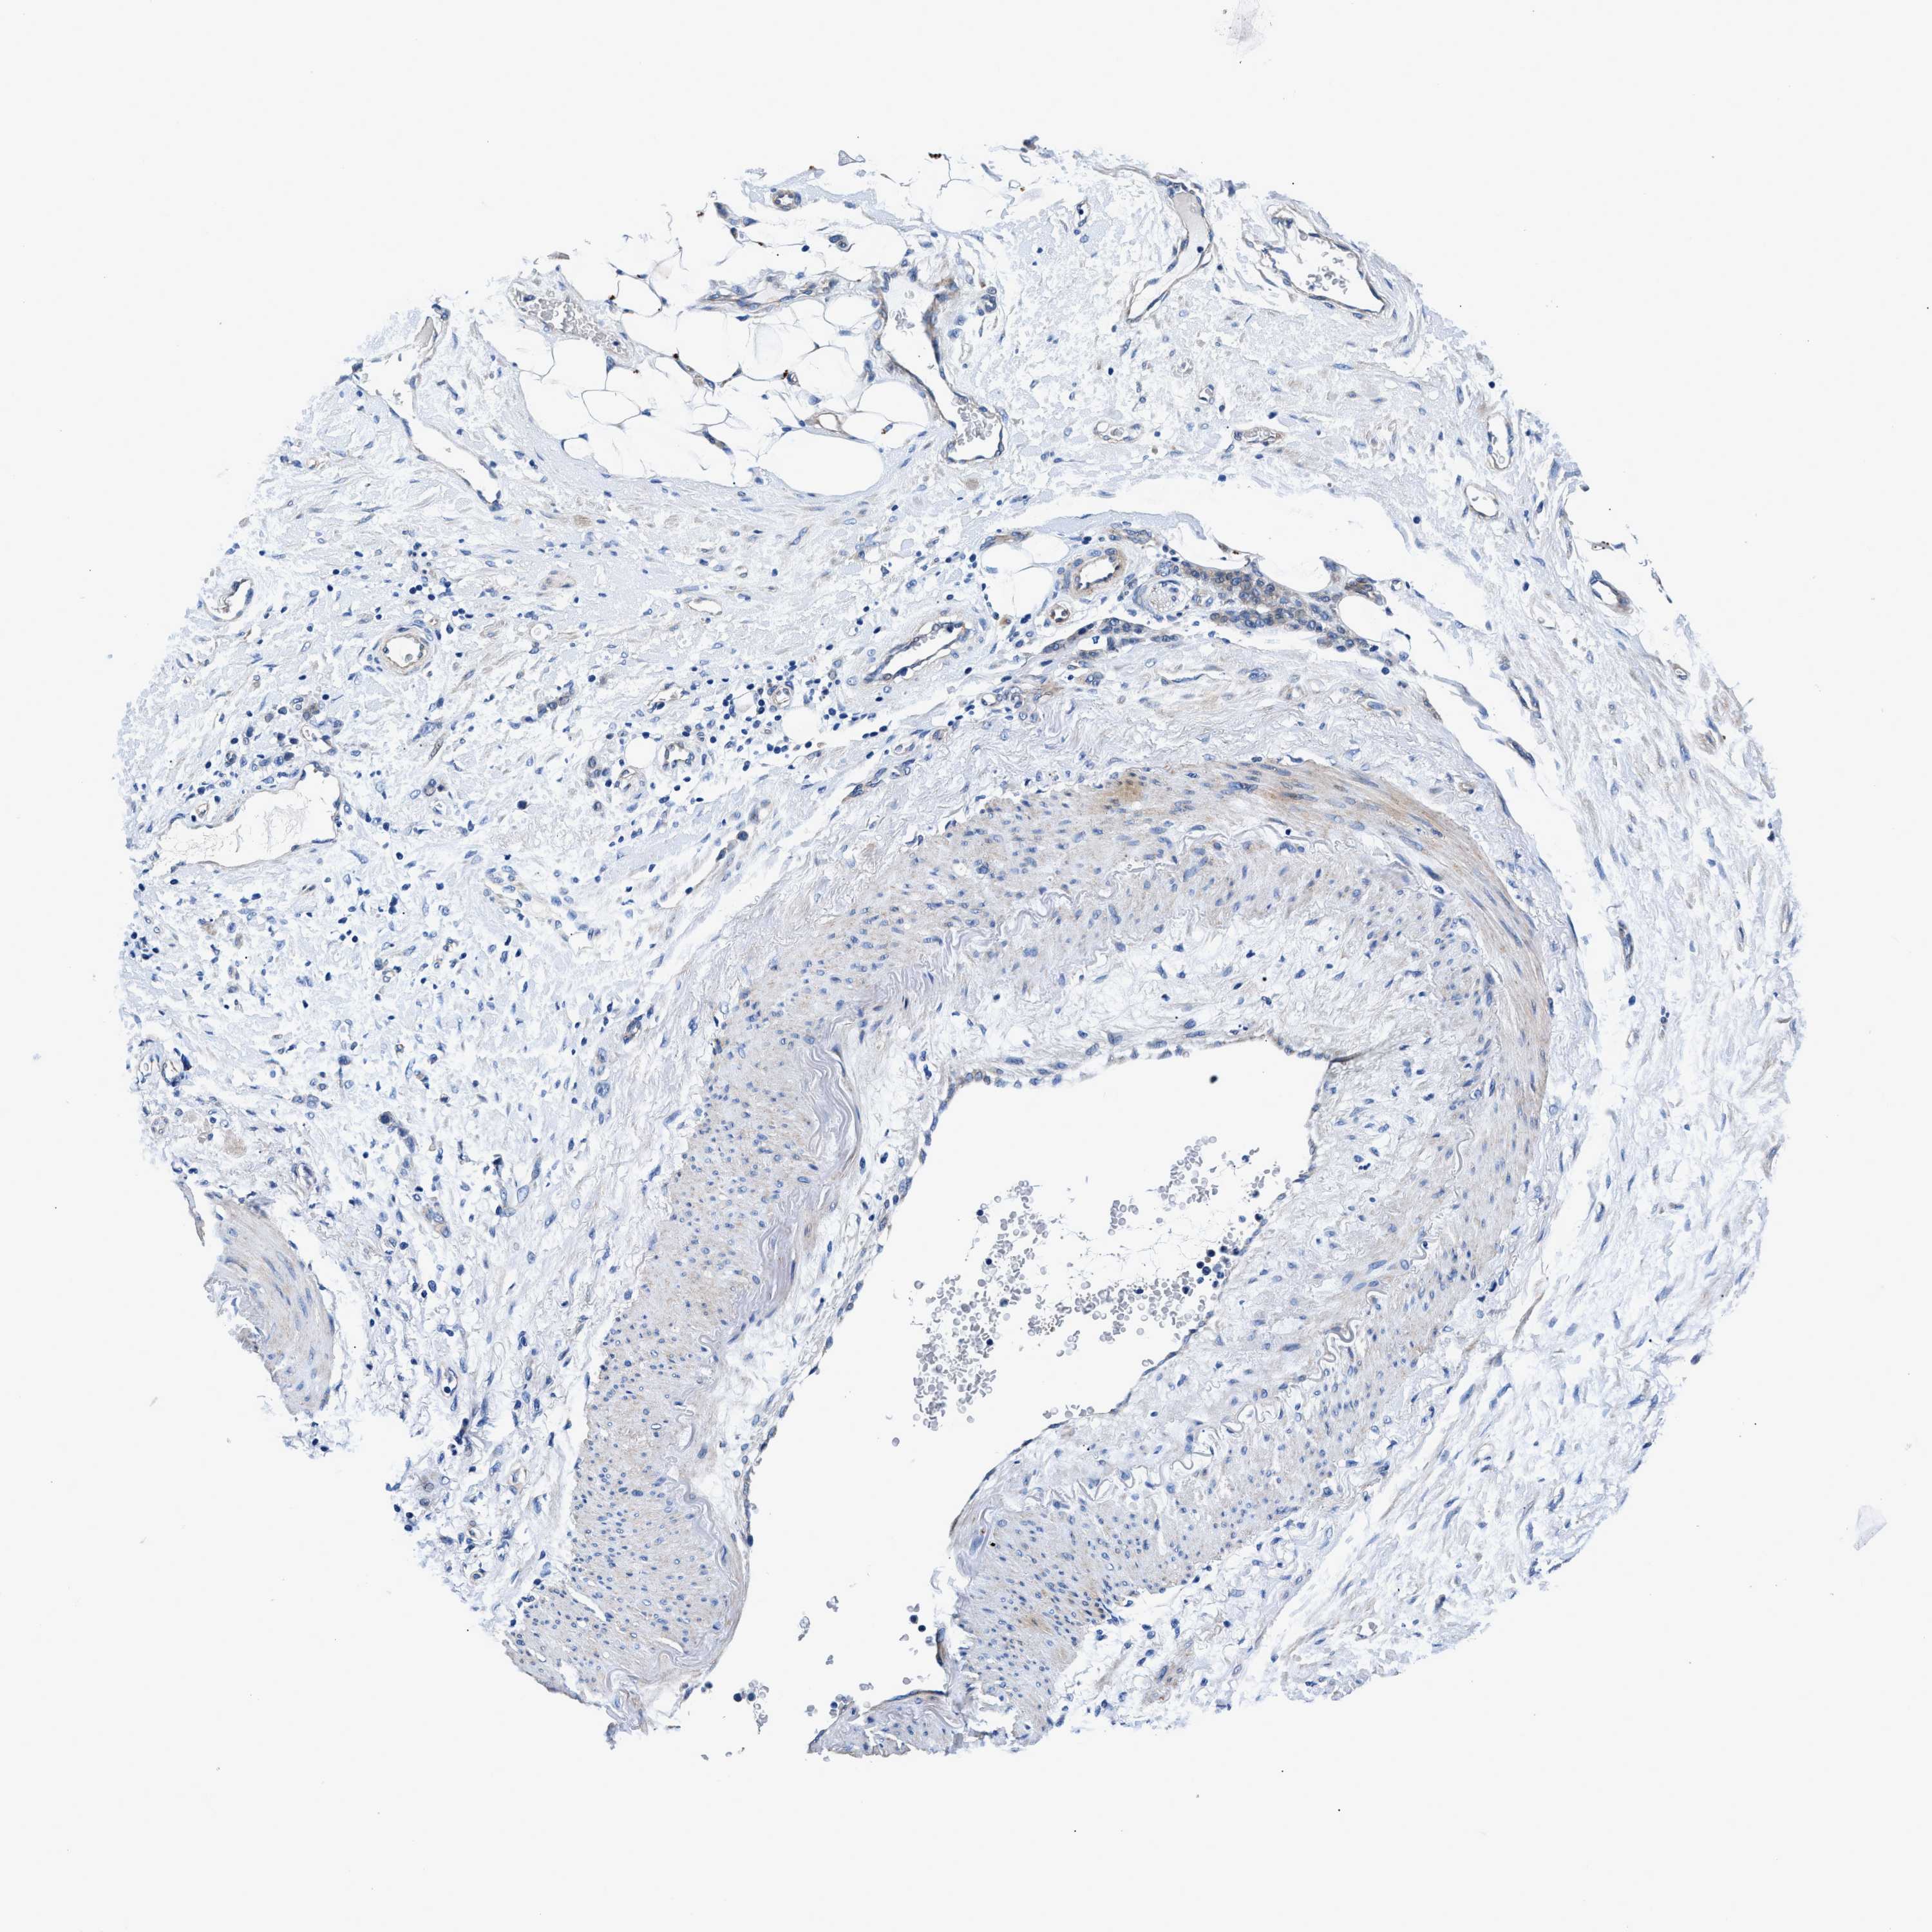

STOMACH CANCER - Protein expressioni

A mouse-over function shows sample information and annotation data. Click on an image to view it in a full screen mode. Samples can be filtered based on level of antibody staining by selecting one or several of the following categories: high, medium, low and not detected. The assay and annotation is described here.

Note that samples used for immunohistochemistry by the Human Protein Atlas do not correspond to samples in the TCGA dataset.

Antibody stainingi

Antibody staining in the annotated cell types in the current human tissue is reported as not detected, low, medium, or high, based on conventional immunohistochemistry profiling in selected tissues. This score is based on the combination of the staining intensity and fraction of stained cells.

Each image is clickable and will lead to virtual microscopy that enables deeper exploration of all samples and also displays staining intensity scores, fraction scores and subcellular localization as well as patient and tissue information for each sample.

Antibody CAB001960

Antibody CAB016353

Staining

High

Medium

Low

Not detected

Intensity

Strong

Moderate

Weak

Negative

Quantity

>75%

75%-25%

<25%

None

Location

Nuclear

Cytoplasmic/membranous

Cytoplasmic/membranous,nuclear

Adenocarcinoma, NOS

Adenocarcinoma, High grade